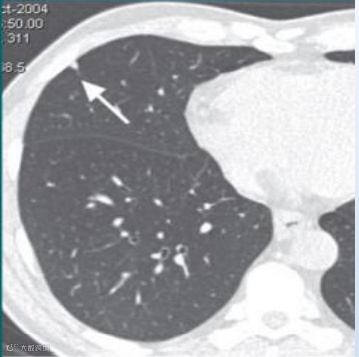

根据美国放射学会(American College of Radiology,ACR)发布的肺部 CT 筛查报告和数据系统(lung imaging reporting and data system, Lung-RADS)1.1版,肺结节可以分为以下几类:

1(阴性):

无结节和确定为良性的肺结节(含良性钙化或脂肪)。

恶性概率:小于1%

2(良性表现或良性生物学行为):

大小或直径无增长,发展为临床侵袭性肺癌的可能性低。

3(良性可能性大):

短期随访可能为良性的结节,包括侵袭性肺癌可能性低的结节。

恶性概率:1-2%

4(可疑恶性):

附加的诊断实验和/或组织标本提示。

4A:恶性概率:5~15%

4B:恶性概率:大于15%